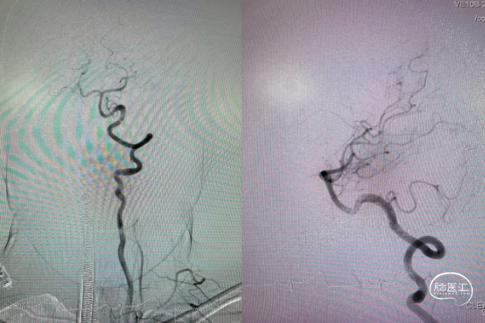

病变部位造影: